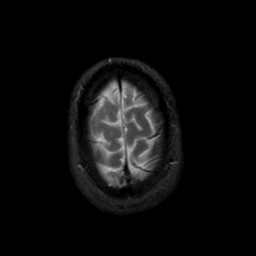

MR Study #18, July 21, 1991 -- Slice #45